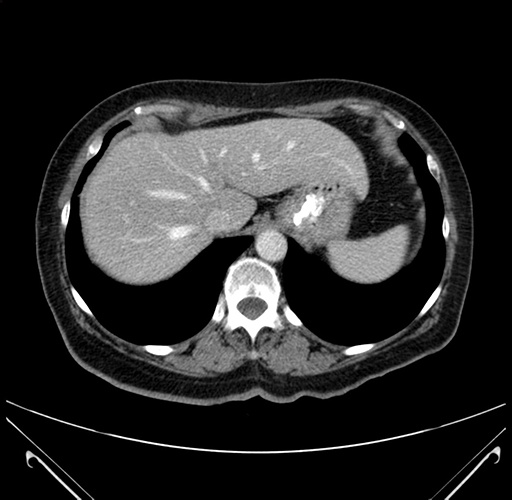

Pre-Chemo: Axial Venous